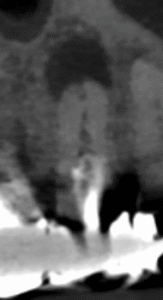

このCBCTの絵でこの結果が想像できるだろうか?

このことから何が言えるか?と言えば、

CBCT画像からのみ根尖部の解剖学的形態・状態を推し量るのは無理である

という臨床的事実だ。

再根管治療は実際にFileを根管の中に入れないとそれに意味があるかどうか?はわからないのである。